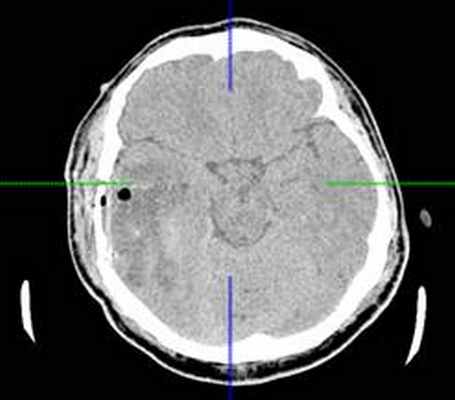

КТ головного мозга с контрастным усилением (24.03.2015): объемное кистозно-солидное образование правой теменно-височно-лобной области. Дислокационный синдром.

22.10.2015 была выполнена операция: микрохирургическое удаление опухоли правой височной доли под интраоперационными навигационным контролем и с интраоперационной фотодинамической терапией.

КТ головного мозга (23.10.2015): не выявило признаков кровоизлияния или каких-либо других хирургических осложнений в области оперативного вмешательства.